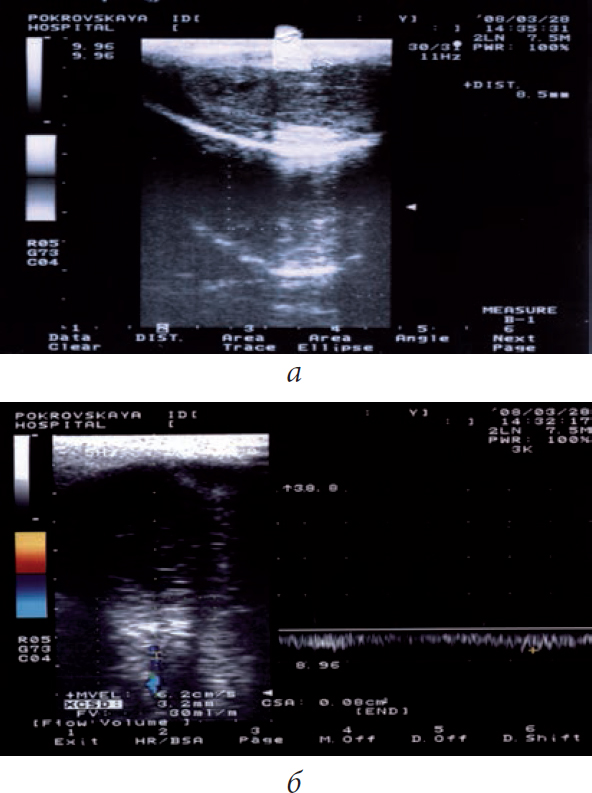

Patients in both groups were simultaneously treated with magnetic-laser therapy by using the AMVL-01 device, which creates an LNP at 2 atm in the flask and causes an erection with 10–20 min duration (Figure 1). The LNP therapy included 10 procedures. In severe erectile dysfunction, a PDE5 inhibitor was prescribed in individually selected doses. The results of treatment were evaluated 6 and 12 months after its onset.

Fig. 1. Diagnosis of curvature of the penis on the apparatus AMVL-01 (apparatus vacuum-laser therapeutic urological) in patient A., 54 years old, with Peyronie's disease. Local negative pressure with maximum discharge in the flask affects the baro-and thermoreceptors of the skin of the penis, enhances microcirculation in its vessels. An insignificant curvature (angle of curvature - 30 degrees) of the penis